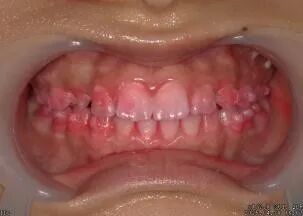

①检查口腔情况 ②拍治疗前口内照片 ③牙菌斑染色

④拍染色后口内照片 ⑤洁牙 ⑥抛光